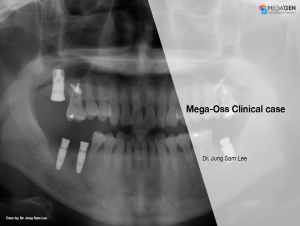

Mega-Oss Clinical Case

Dr. Jung Sam Lee,Immediate loading,Bone regeneration,Mandibular Posterior,#46,#47,GBR,AnyOne External,Mega-Oss,Clinical case

English

2019-10-01

PDF

1.14 Mb

Clinical cases

197